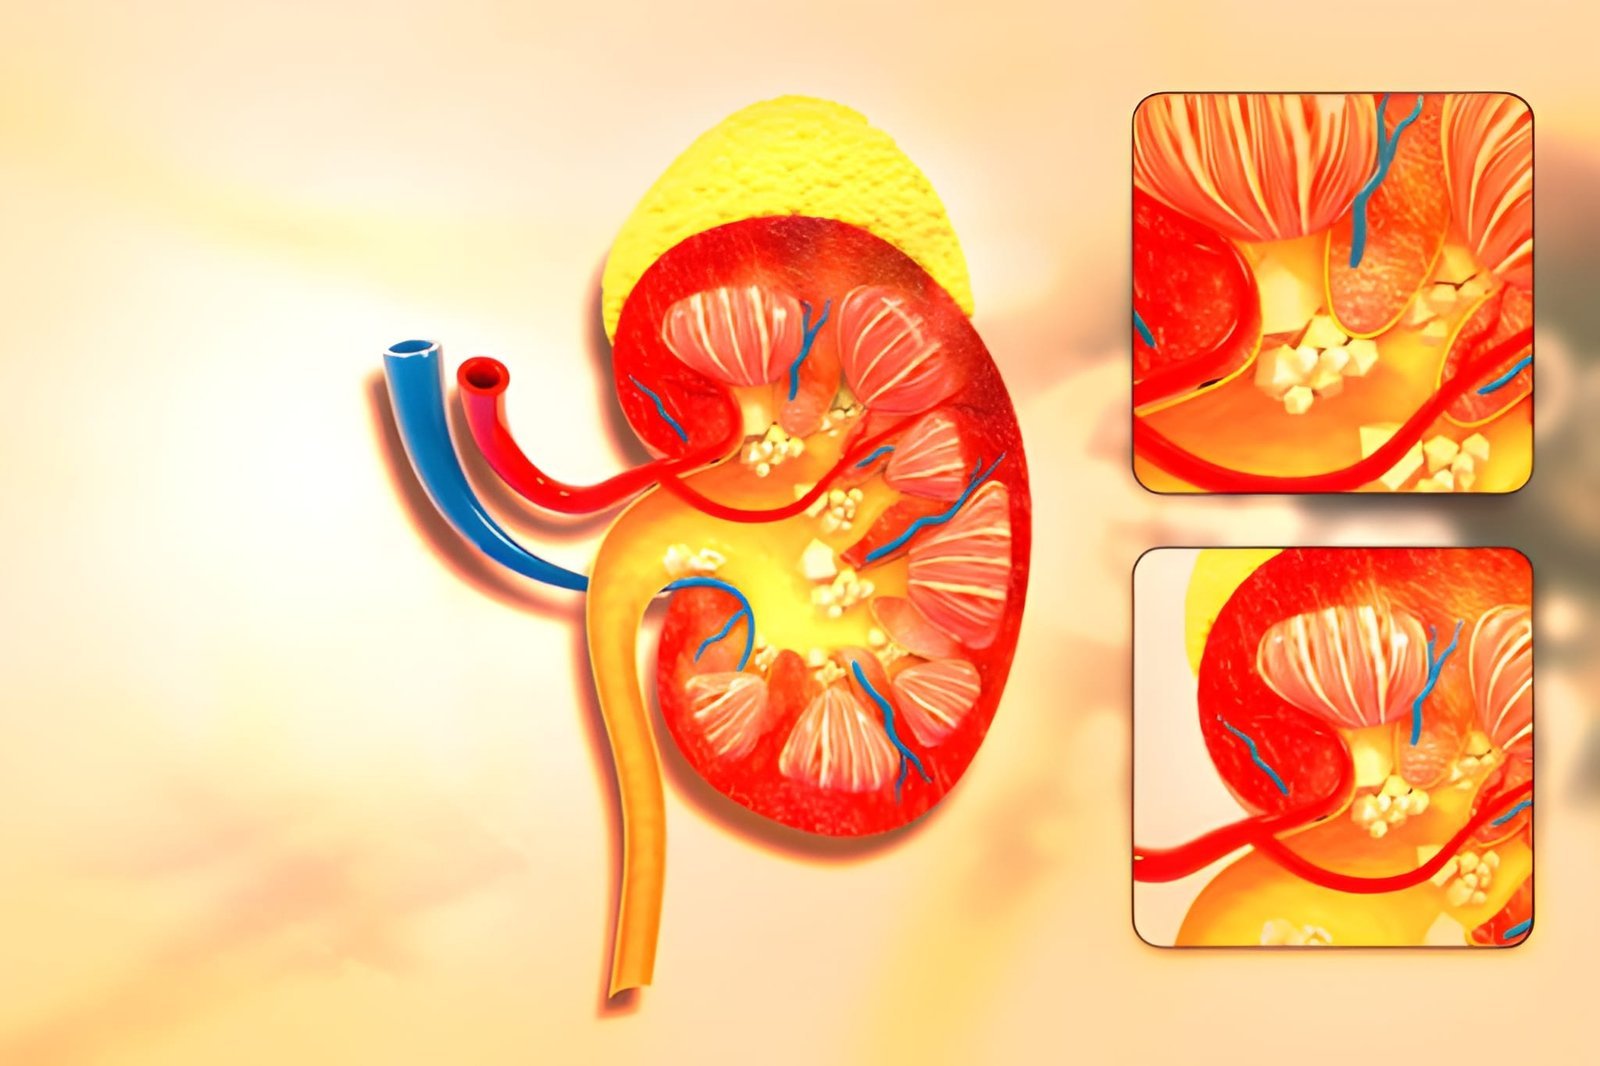

Percutaneous Nephrolithotomy (PCNL) is a minimally invasive surgical procedure used to remove kidney stones that are too large to pass naturally or cannot be treated effectively with other methods.

The term “percutaneous” means through the skin. During this procedure, a small incision is made in the back to create a pathway directly to the kidney. Through this pathway, the surgeon inserts specialized instruments through a thin tube to locate, break, and remove the kidney stones.

When large kidney stones block multiple branches of the kidney's collecting system (known as staghorn stones).

The surgeon begins by inserting a special needle into the kidney’s urine-collecting chamber (calyx) using imaging guidance such as X-ray, CT scan, or ultrasound.

Specialized instruments are passed through this tube to break the stones into smaller pieces and remove them.